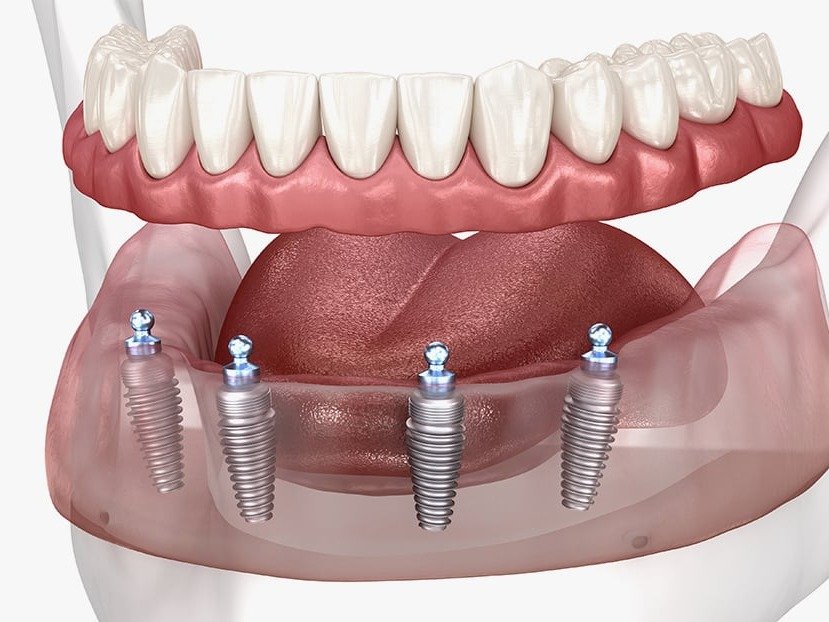

Full Arch

Deja atrás las prótesis removibles

El tratamiento Full Arch representa un hito en implantología para pacientes que han perdido múltiples piezas dentales o que desean dejar atrás las prótesis removibles. Con este enfoque, colocamos implantes dentales que soportan una prótesis fija completa, lo que te permite salir de la clínica con dientes funcionales y estéticos el mismo día de la cirugía, cuando tu caso lo permite. Mi compromiso como cirujano es garantizar una rehabilitación personalizada y predecible, devolviéndote no solo una sonrisa natural, sino también la confianza para disfrutar de tu vida diaria sin limitaciones.